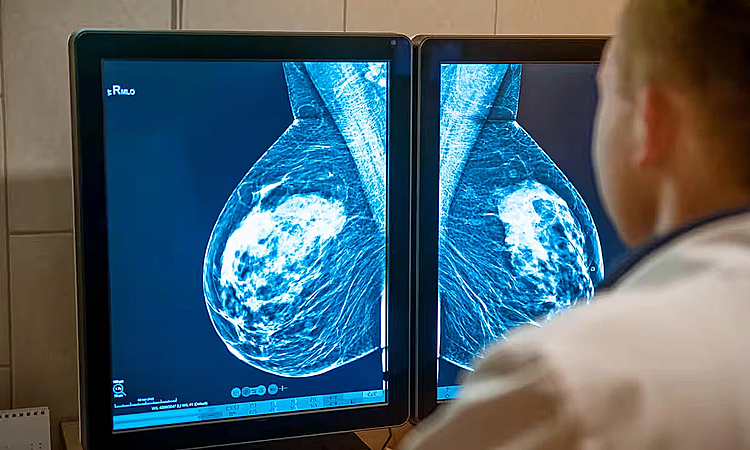

Hà NộiSau một năm sờ thấy khối u bất thường tại vú, người đàn ông 61 tuổi mới đi khám, bác sĩ phát hiện ung thư vú, bệnh ít gặp ở nam giới.

Ngày 11/11, đại diện Trung tâm Y học hạt nhân và Ung bướu, Bệnh viện Bạch Mai, cho biết bệnh nhân sờ thấy một khối cứng nhỏ ở vú trái nhưng chủ quan, không đi khám vì “nghĩ đàn ông thì làm gì bị ung thư vú”.

Gần đây, khối u lớn dần, kèm theo đau âm ỉ, ông mới đi kiểm tra. Các bác sĩ chỉ định sinh thiết, kết quả mô bệnh học cho thấy tổn thương ở vú trái là ung thư biểu mô xâm nhập. Bệnh nhân được nhập viện để tiếp tục đánh giá, điều trị theo phác đồ chuyên khoa.